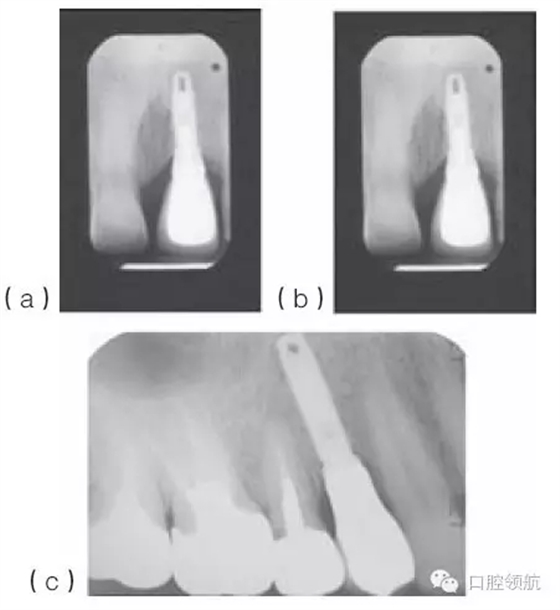

種植體適當(dāng)?shù)那蓄i/ 頸向位置,有利于建立逐漸過渡的外形和正常的穿齦形態(tài)。種植體切頸/牙合頸向的定位,很大程度上取決于現(xiàn)存骨的位置(圖10.33a~c),以及滿足美學(xué)需求的頸部過渡形態(tài)。因?yàn)榉N植體的平臺(tái)接口為小直徑的圓形,而齦緣的修復(fù)體截面為直徑較大的不規(guī)則幾何形態(tài),中間需要一定的過渡才能滿足美學(xué)的需求。一般來說,種植體植入到鄰牙釉牙骨質(zhì)界稍下方,以使所需的形態(tài)學(xué)改變逐步發(fā)生(圖10.34)。

圖10.33 (a)金屬烤瓷冠粘結(jié)后的根尖片。(b)種植體位于鄰牙釉牙骨質(zhì)界根方3mm的根尖片。切嵴到種植體頂部的距離太大,導(dǎo)致種植體金屬部件可能承受較大的力。(c)種植體植入到嚴(yán)重骨吸收的上頜第一前磨牙區(qū)。種植體到面的距離幾乎等于種植體的長(zhǎng)度。